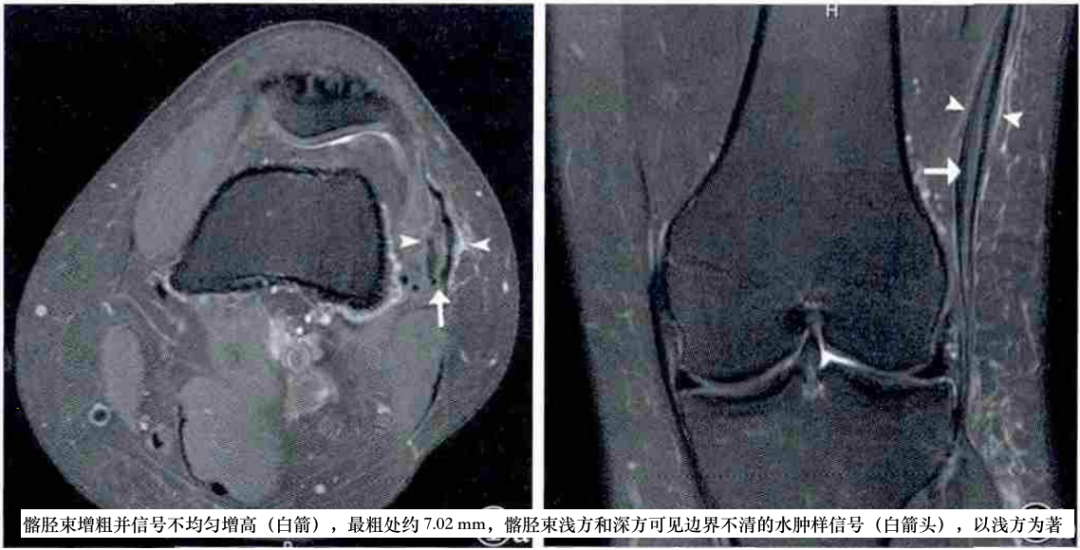

①股骨外侧髁侧方、近侧或远侧的境界不清的异常信号;②髂胫束表面或深部异常信号;③髂胫束与股骨外侧髁侧方、近侧或远侧之间局限性积液;④髂胫束位于股骨外髁水平的部分增厚、呈波浪状或连续性中断,常伴有胫骨Gerdy结节撕脱骨折和髂胫束附着处水肿;⑤关节腔积液;⑥其他异常(如半月板撕裂),其中1~3最具特征性。